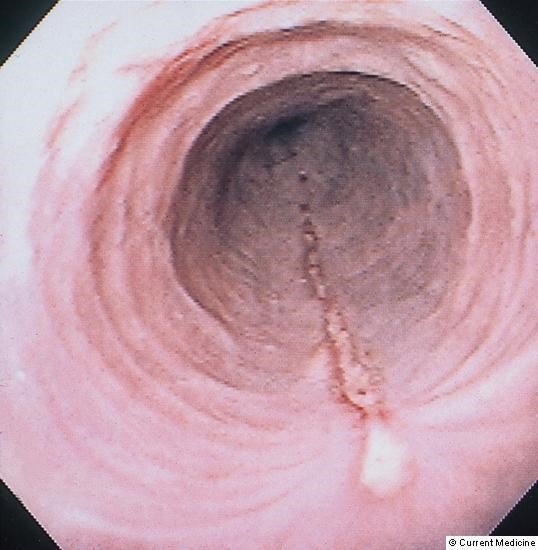

Diaqnozun dəiqiləşdirilməsi üçün kontrastlı Rentgenoloji müayinələr, KT və çox ehtiyatla endoskopiya edilir.

- Kontrastlı Rh-qrafiya - diaqnozu dəqiqləşdirən müayinədir.

- Endoskopiya - divertikulun perforasiyası təhlükəsinə görə çox ehtiyatla aparılmalıdır.

- Rentgenoqrafik divertikul görünməsi